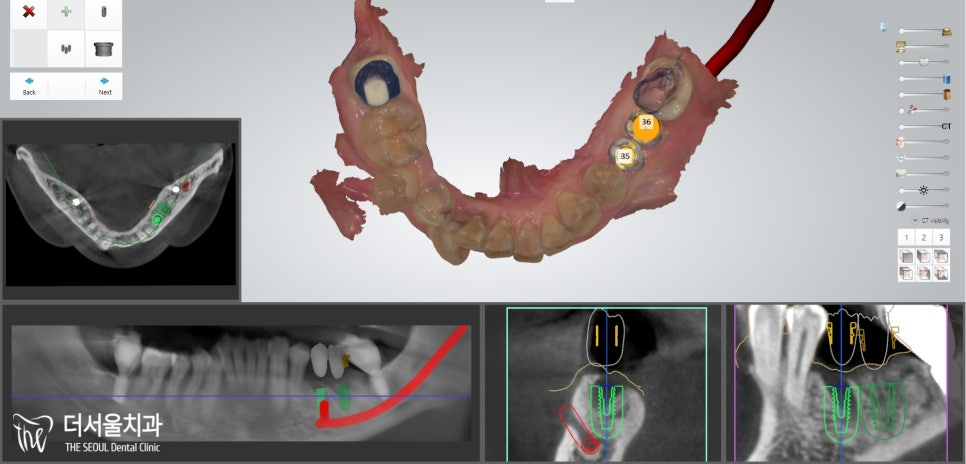

편안한 식립을 돕기 위해

컴퓨터분석임플란트 를 하기로 계획을 세웠습니다.

『컴퓨터분석임플란트 로 보다 편안하게』

컴퓨터분석임플란트 를 심기 전,

내부 조직과의 위치 관계를 확인해야겠죠?

하악은? 하치조신경관~

초록색 선이 신경관의 위치입니다.

이럴 땐 더더욱 컴퓨터분석임플란트 를 해야 됩니다.

정확한 위치 및 거리 계산을 통해

단 0.001mm의 오차도 발생하지 않도록 진행을 해야 되죠.

자칫 삐끗했다간 신경관 손상 및 마비로

이어질 수 있는 큰 문제이기 때문이죠.